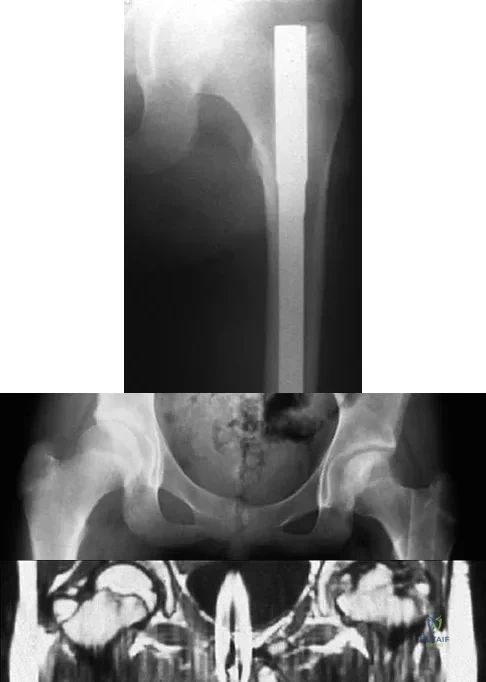

Question 304High Yield

Figure 19 shows the radiograph of a 45-year-old woman who has a painful nonunion. Treatment should consist of

Explanation

The radiograph reveals a reverse obliquely subtrochanteric/intertrochanteric fracture. Open reduction and internal fixation should be accomplished with a 95-degree fixed angle device. An intramedullary nail with screw fixation into the head is another possible technique. Either method should correct the varus deformity. Exchange of a high-angled screw and plate device to a longer side plate and bone grafting does not afford any improvement in the mechanical stability. Hardware removal and retrograde intramedullary nailing is not indicated for this level of a proximal femoral injury. Placement of an implantable bone stimulator may change local biologic factors but would not enhance mechanical stability. The patient's femoral head is intact without signs of collapse; therefore, hardware removal, proximal femoral resection, and total hip arthroplasty are not warranted. Haidukewych GJ, Israel TA, Berry DJ: Reverse obliquity fractures of the intertrochanteric region of the femur. J Bone Joint Surg Am 2001;83:643-650.

References:

- Koval KJ, Zuckerman JD: Intertrochanteric fractures, in Rockwood & Green's Fractures in Adults, ed 5. Philadelphia, PA, Lippincott Williams and Wilkins, 2001, pp 1635-1681.